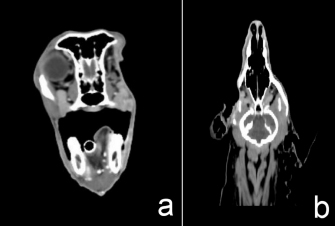

After radiation

After complete radiation, the dog had normal clinical signs with some hair loss at the radiation site. The CT images showed no detectable recurrent tumor or abnormal contrast enhancement in the right retrobulbar and zygomatic areas. After radiation treatment for 11 months, the CT images showed no detectable recurrent tumor or abnormal contrast enhancement in the right retrobulbar and zygomatic areas (Fig. 5).

Fig. 5. After 11 months of complete radiation treatment, transverse (a) and dorsal (b) computed tomographic images in the right retrobulbar, caudal maxilla, zygomatic, and temporal areas without mass effect or abnormal contrast enhancement.